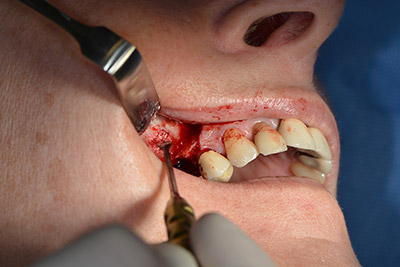

The classic incision (crestal, buccal relief) and the preparation of the mucoperiosteal flap enabled a good overview.

An absorbable membrane was used as the barrier in the buccal direction and covered the augmentation. Finally, saliva-proof sutures were placed (Fig. 15 to 19).